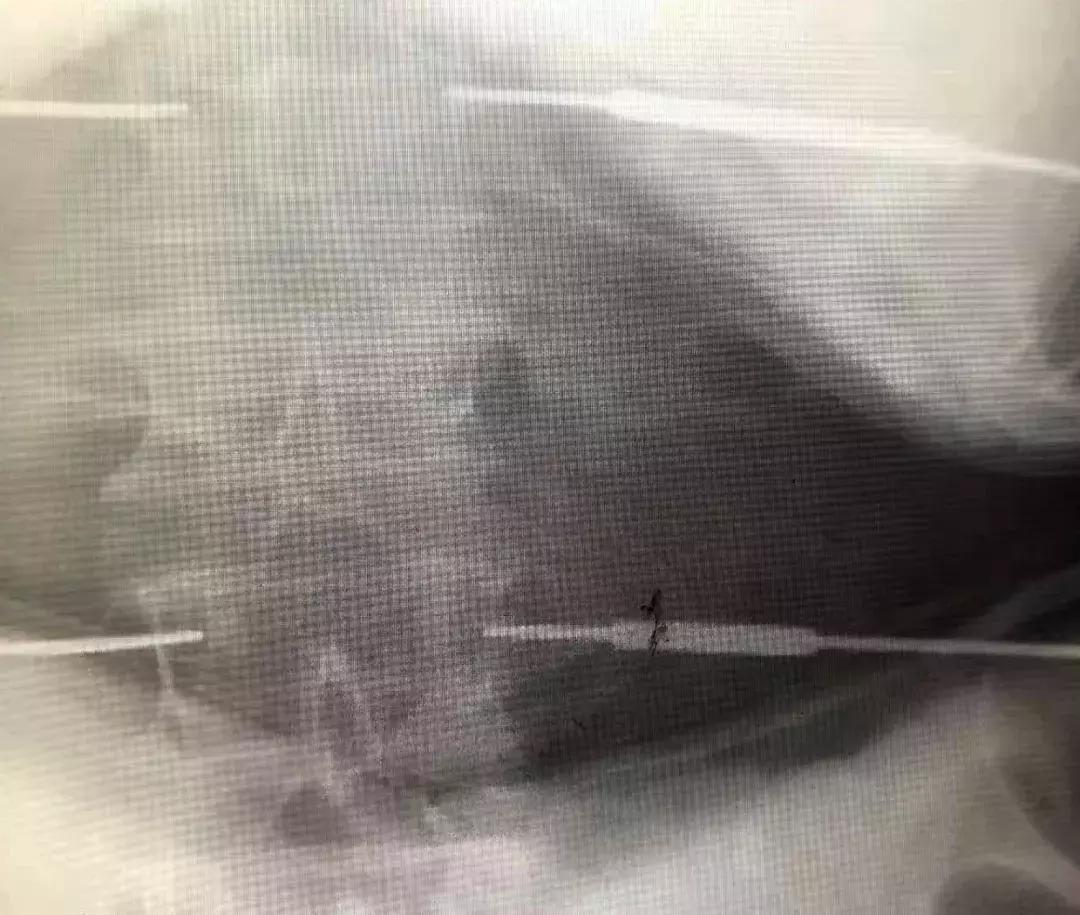

术前第二腰椎压缩性骨折,压缩1/2椎体